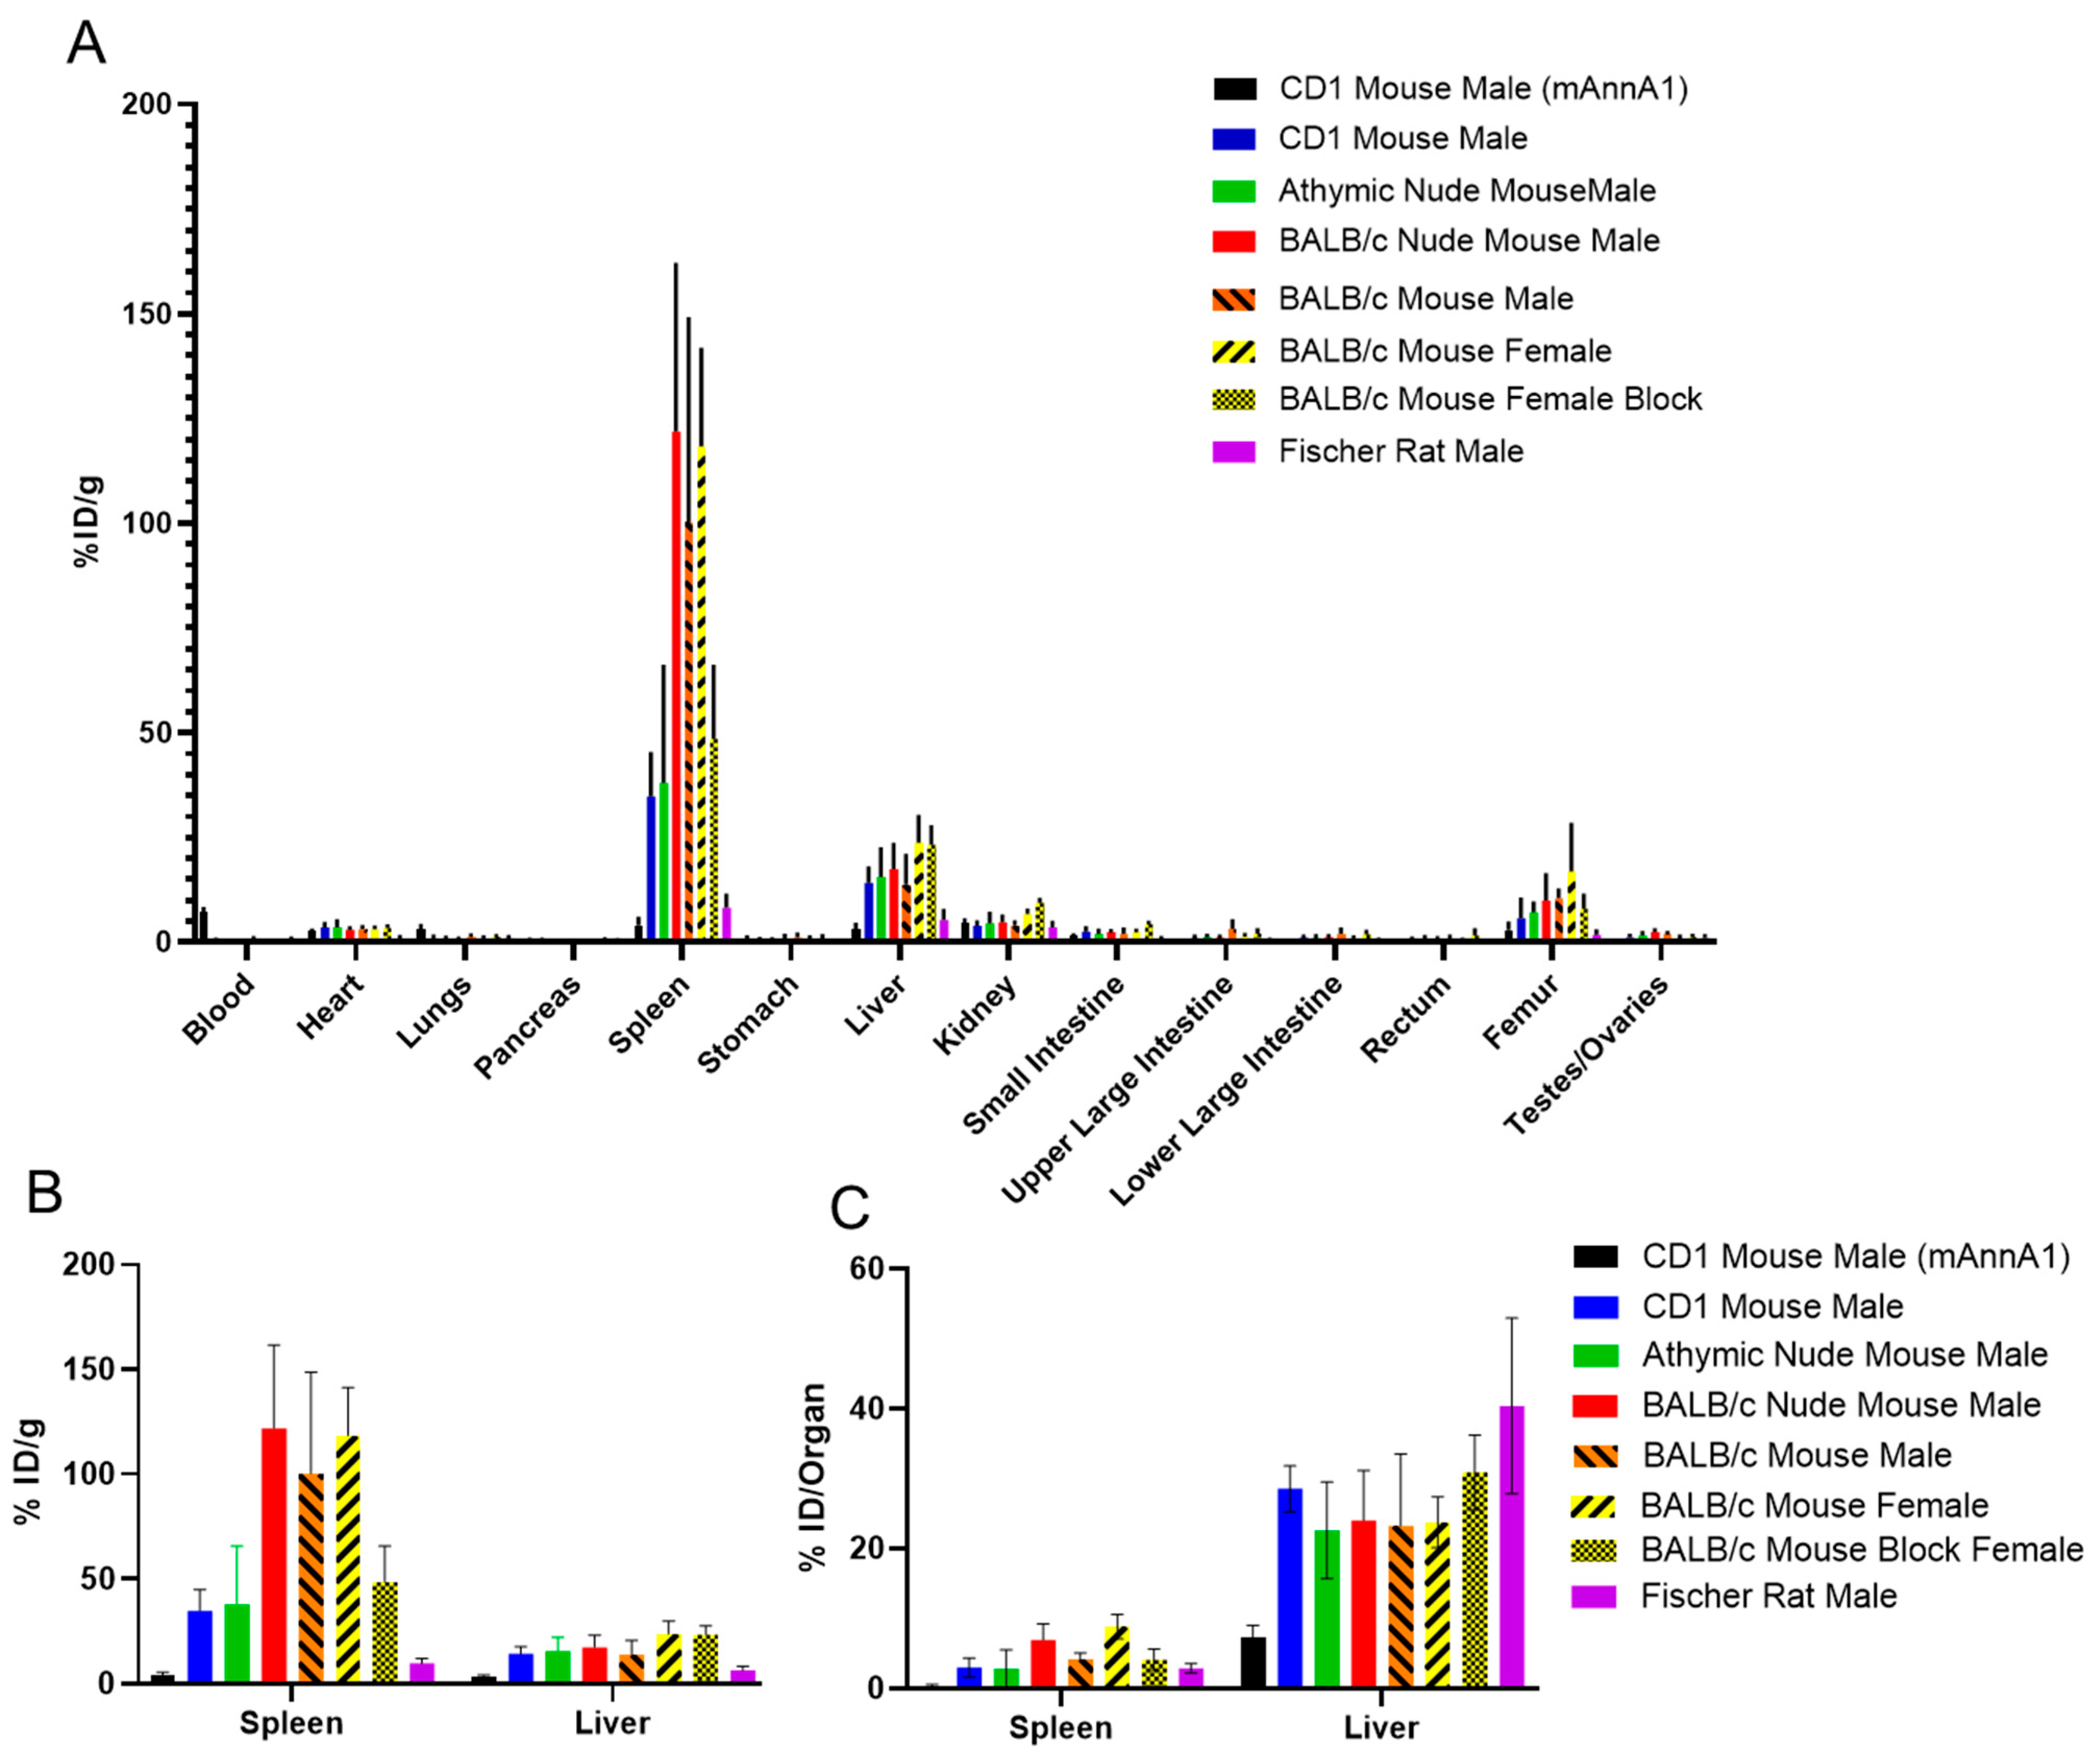

2. Results

- Sharma, S.K.; Chow, A.; Monette, S.; Vivier, D.; Pourat, J.; Edwards, K.J.; Dilling, T.R.; Abdel-Atti, D.; Zeglis, B.M.; Poirier, J.T.; et al. Fc-Mediated Anomalous Biodistribution of Therapeutic Antibodies in Immunodeficient Mouse Models. Cancer Res. 2018, 78, 1820–1832. [Google Scholar] [CrossRef]

- Sharma, S.K.; Suzuki, M.; Xu, H.; Korsen, J.A.; Samuels, Z.; Guo, H.; Nemieboka, B.; Piersigilli, A.; Edwards, K.J.; Cheung, N.V.; et al. Influence of Fc Modifications and IgG Subclass on Biodistribution of Humanized Antibodies Targeting L1CAM. J. Nucl. Med. 2022, 63, 629–636. [Google Scholar] [CrossRef]